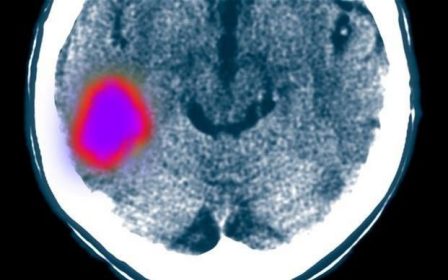

وقتي سكته مغزي اتفاق مي افتد، سلول هاي عصبي در ناحيه آسيب ديده مغز مي ميرند و التهابي را ايجاد مي كنند كه در نتيجه آن، سلول ها سيستم ايمني بدن از جمله مونوسيت ها جذب مي شوند.

مونوسيت ها نوعي سلولهاي سفيد خون هستند كه از مغز و استخوان توليد مي شوند و پس از حركت به سمت ناحيه ملتهب، سبب بهبود ناحيه آسيب ديده مغز مي شوند.